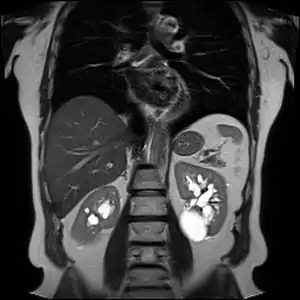

| Renal cyst of the left kidney (hyperintense area) as shown on MRI. | |

Numerous renal cysts are seen in the cystic kidney diseases, which include polycystic kidney disease and medullary sponge kidney.